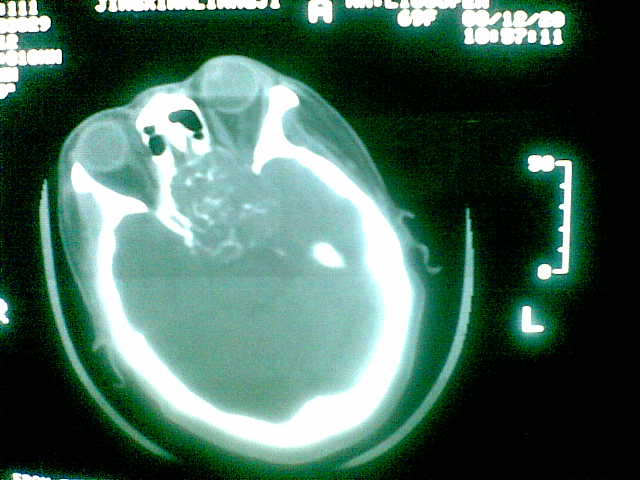

69岁 女 主因头痛就诊。大家看看起源于哪里啊

起源于斜坡,考虑脊索瘤.

起源于斜坡,考虑脊索瘤. 很典型

多为脊索瘤。起源于斜坡!